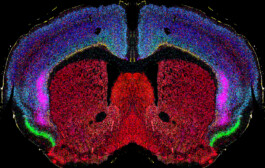

Le projet vise à mieux comprendre et améliorer les fonctions cognitives, comme la mémoire et l’attention, chez les personnes souffrant de troubles psychopathologiques, notamment celles atteintes du syndrome 22q11.2. Les chercheurs étudient à la fois des approches non médicamenteuses, comme la stimulation cérébrale (tACS), et des pistes pharmacologiques ciblant une région clé du cerveau appelée le claustrum, impliquée dans la mémoire de travail. Grâce à des outils d’imagerie cérébrale de pointe et à des mesures en conditions réelles, ils cherchent à relier les mécanismes cérébraux observés chez l’animal et chez l’humain aux difficultés concrètes rencontrées au quotidien, comme l’isolement social ou les troubles de l’attention. L’objectif final est d’identifier des interventions sûres et efficaces pouvant être rapidement appliquées en clinique.